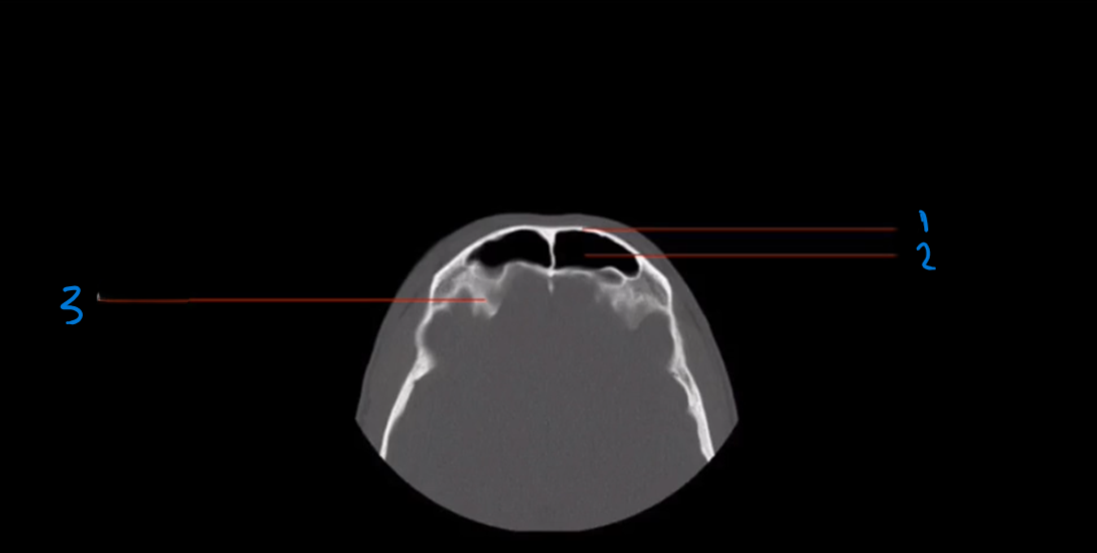

What is landmark #1 called?

Nasal bone

What is landmark #2 called?

Perpendicular plate, ethmoid bone

What is landmark # 3 called?

Zygoma